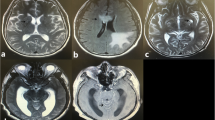

There were 48 patients in the NSDB group and 72 in the SDB group. The patients in the NSDB group were characterized by normal brain imaging (Fig. 1A). The patients in the SDB group were primarily characterized by CM-related brain damage(Fig. 1B). The characteristics of the NSDB and SDB groups are summarized in Table 2. In patients with CM alone, the BMI of patients in the SDB group was significantly lower than that in the NSDB group (Table 2).

MRI in NSDB and SDB groups: A MRI in NSDB group; B MRI in SDB group (NVM); C MRI in SDB group (VM); red arrows cryptococcal meningitis-related brain damage, yellow arrows ventriculomegaly. MRI magnetic resonance imaging; NSDB non-structural damage of the brain; SDB structural damage of the brain; NVM non-ventriculomegaly; VM ventriculomegaly

Characteristics of Patients with Alterations in Cerebral Ventricles

In the SDB group, there were 27 patients with and ventriculomegaly (VM; Fig. 1C). The patients in the SDB group were divided into the non-VM (NVM) and VM groups. The general characteristics of patients in these groups are enumerated in Table 5. The age of patients in the NVM group (45.27 ± 12.45 years) was significantly lower than that in the VM group (55.89 ± 14.30 years; P < 0.01). The results of the analysis of the characteristics of CSF and PB in these two groups are summarized in Table 6. Compared with the NVM group, the levels of PB-Hb (P < 0.05), PB-ALB (P < 0.05), and PB-K (P < 0.01) were significantly decreased in the VM group, and the levels of PB-UA (P < 0.05) were significantly increased in the VM group. Of note, hypokalemia is recognized as a common side effect of AmpB [33]. To ascertain whether AmpB led to alterations in the peripheral metabolism, the patients in the SDB group were divided into two groups, namely, the non-received AmpB group and the received AmpB group. The results revealed no significant difference in the levels of PB-K, PB-Hb, PB-ALB, and PB-UA (Table 7).